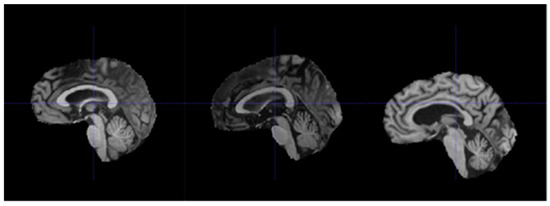

Removal of irrelevant tissues such as those of the eyes, nose, and mouth from brain MRIs, also known as skull-stripping, is essential in reducing the amount of noise within each MRI volume. Iglesias et al. [42] proposed an automated skull-stripping algorithm known as ROBEX that was shown to produce reliable segmentations of the tissues belonging to the brain. With the ROBEX algorithm, all MRI scans in the dataset were skull-stripped to obtain volumes containing just the brain tissues; an example is shown in Figure 7.

Figure 7.

Before (left) and after (right) performing ROBEX skull-stripping.